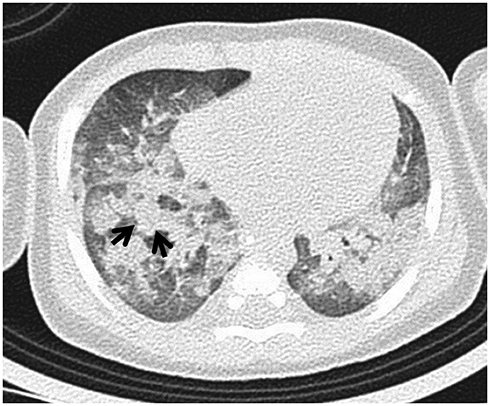

Computed Tomographic Features of Lung Parenchyma Over Time after Cardiopulmonary Resuscitation

To identify the key CT features of lung parenchyma over time after cardiopulmonary resuscitation (CPR).

In total, 72 patients underwent CT after CPR. Because the median time from return of spontaneous circulation (ROSC) to CT was 1 h 3 min, we divided patients into two groups: ≤ 1 h (group 1) and > 1 h (group 2), based on the ROSC to CT time. We analyzed and compared various lung parenchymal CT findings between groups.

Each group included 36 patients. Using statistical analysis, we identified seven statistically significant imaging features. Gradient (p = 0.010), lobular gradient (p = 0.017), diffuse pattern (p = 0.000), upper distribution (p = 0.032), and peripheral portion sparing (p = 0.000) were more common in group 1 than in group 2. Dependent density (p = 0.010) and lobular consolidation (p = 0.010) were more common in group 2 than in group 1.

The gradient and lobular gradient tended to disappear over time after ROSC. In terms of distribution, a diffuse pattern with upper predominance and peripheral portion sparing tended to disappear over time. However, the dependent density and lobular consolidation tended to increase over time in the lung parenchyma after CPR.